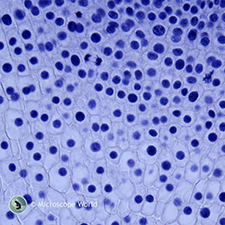

| Spinal Cord c.s. | Spirogyra | |